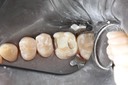

Gary Umeda #18,19,20 pre-op

Gary Umeda #18, 19, 20 prep

Gary Umeda #18, 19, 20 try in